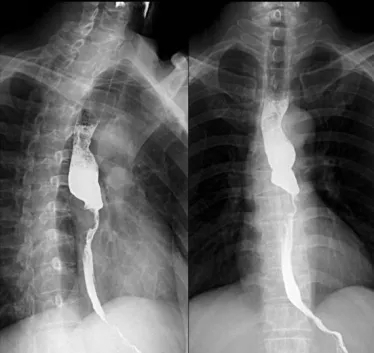

吞钡检查:食管吞钡检查是很常见的检查。可以查看食管是否通畅,肿瘤的位置在哪,食管的形状是否有变化等。如图一。